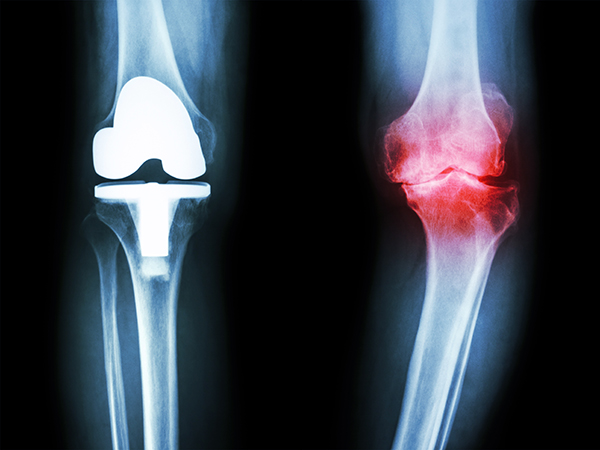

Fig 4: Erosion of cartilage to expose underlying bone is initially very painful.

Damage can progress to erosion of cartilage, which initially is intensely painful. In time, however, granulation tissue can fill the erosion and, lacking nerve ending leads to, tolerance or even a cessation of pain (fig 4).